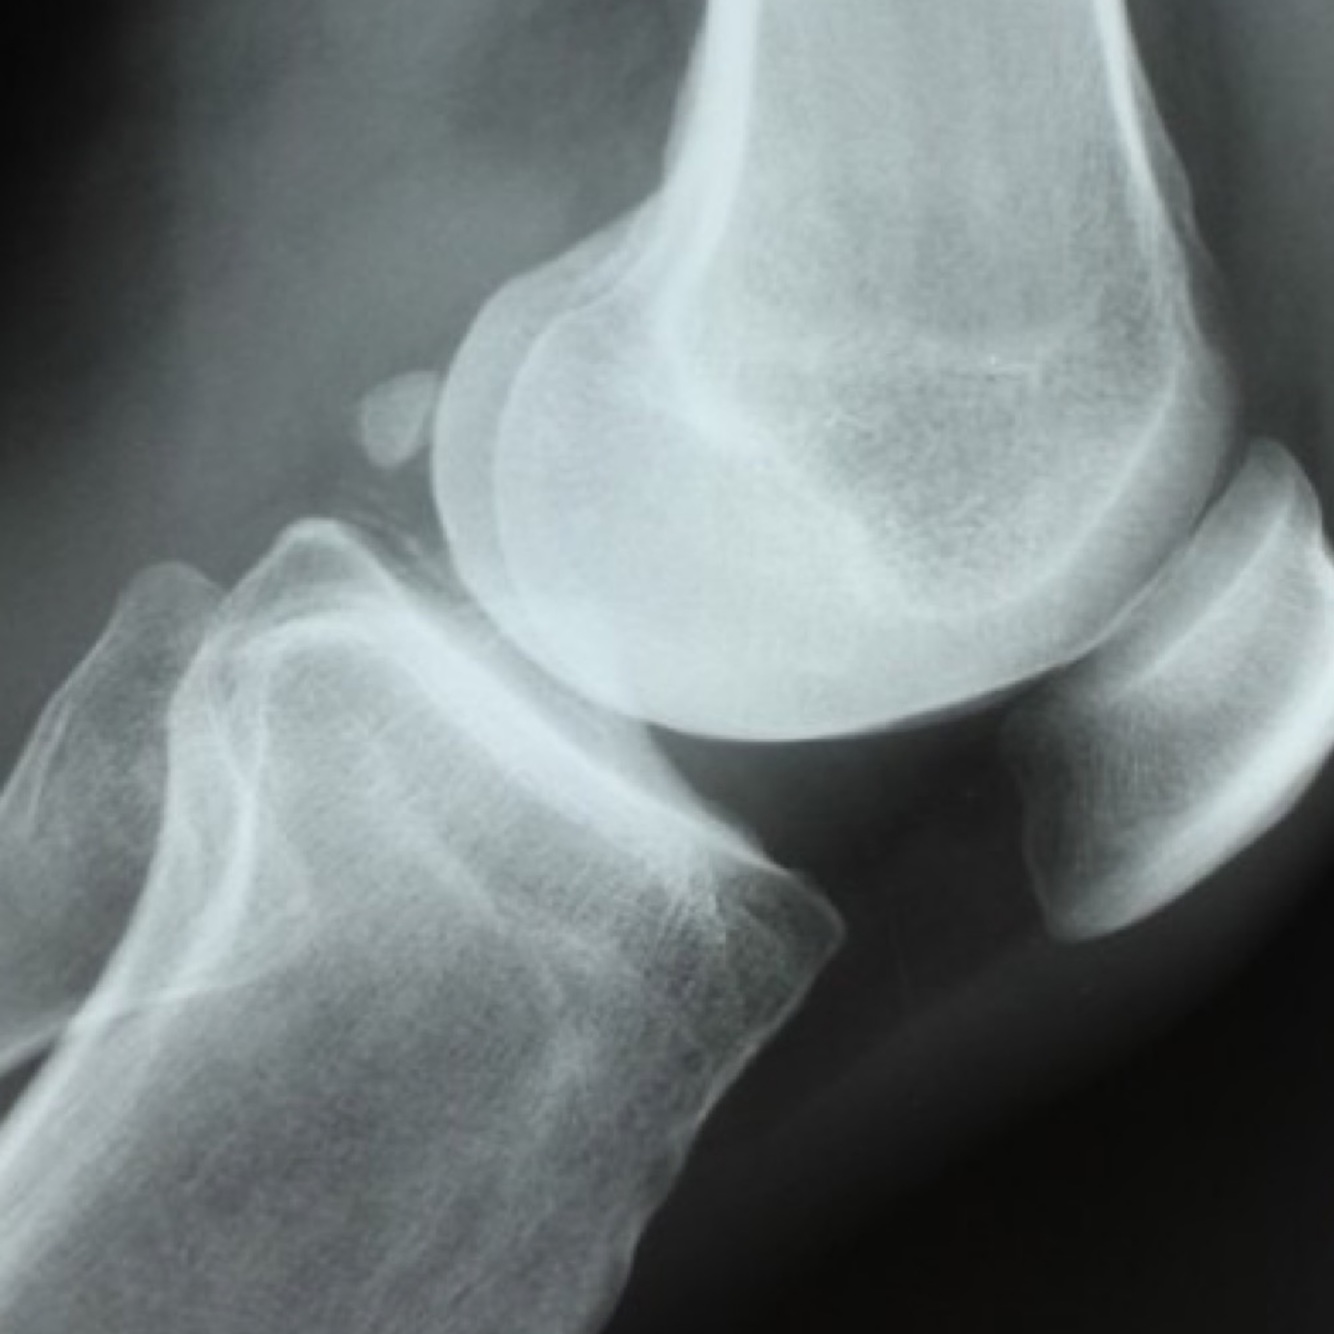

Qu’est-ce que je vois dans ma projection lat du genou

Genou fléchi entre 20 ̊-30 ̊

• Position de la rotule (baja, alta).

• Articulation fémoro-rotulienne de profil

• Attaches tendineuses du système extenseur

• Os fabella

• Évaluation de l’espace supra- patellaire à la recherche d’épanchement